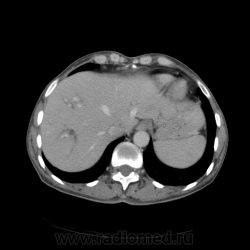

КТ ОБП - гепатомегалия, признаки панкреатита

МРТ ОБП - от 16.12.10 гепатомегалия, расширение панкреатических протоков.